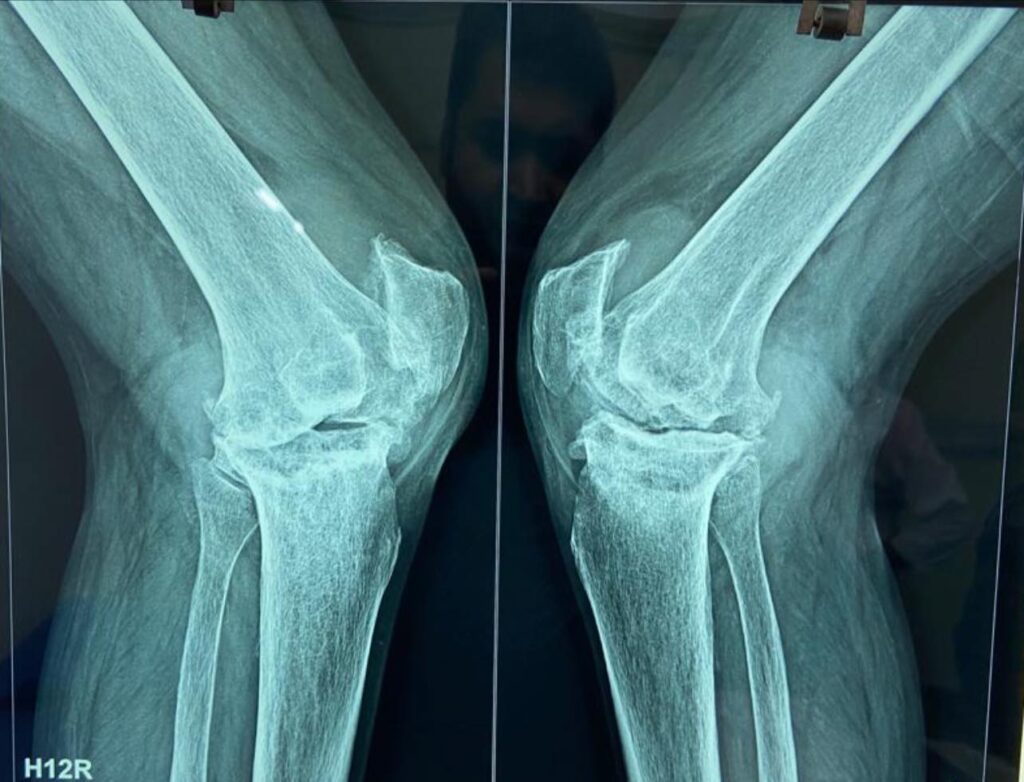

Most neck of femur fractures are treated with partial or total jointreplacement surgeries. however doing so limits active lifestyle in younger individuals. Especially in the Indian system of living. that is why it’s important to take such fractures as surgical emergencies in young people like this 43 year old woman and treat them with screw […]